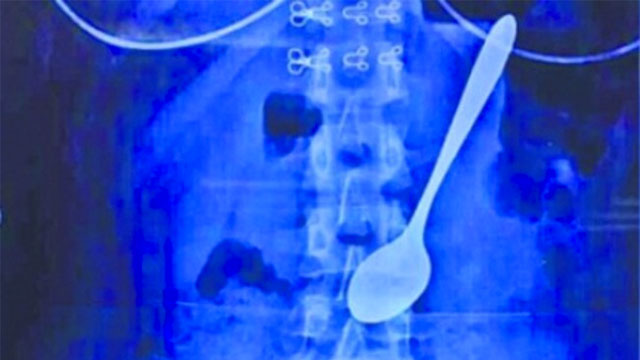

Dokter di Tiongkok Keluarkan Sendok dari Tubuh Mahasiswi

Foto: shanghaiist

MerahPutih Internasional - Para dokter di sebuah rumah sakit di Tiongkok berhasil mengeluarkan sebuah sendok berukuran 14 sentimeter dari perut seorang mahasiswi.

Kala itu, secara tiba-tiba seorang teman melompat di belakang punggung Weiwei untuk mengagetkannya. Namun, hal yang terjadi berikutnya sungguh di luar dugaan. Karena begitu kagetnya Weiwei, sendok es krim dari logam berukuran 14 sentimeter yang saat itu digunakan tanpa sengaja tertelan.

Weiwei memutuskan untuk pergii ke rumah sakit sehari setelah insiden itu. Setelah melakukan diagnosa, dokter berhasil mengeluarkan sendok itu keluar lewat tenggorokan Weiwie dalam sebuah operasi kecil yang berlangsung hanya dalam waktu 10 menit.